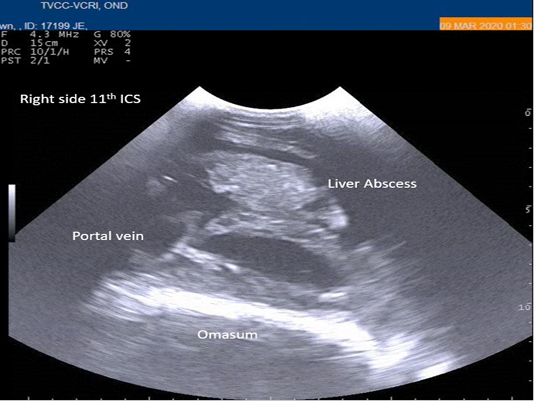

Figure 2

Percutaneous ultrasonography of right-side abdomen at 11th inter coastal space showed liver hyperechoic foci with anechoic cavity.